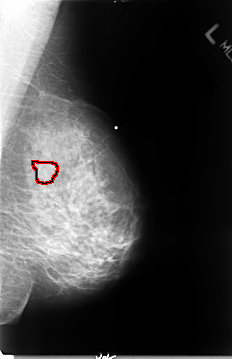

B_3072_1.RIGHT_MLO

FILE: B_3072_1.LEFT_MLO.OVERLAY

TOTAL_ABNORMALITIES 1

ABNORMALITY 1

LESION_TYPE MASS SHAPE IRREGULAR MARGINS OBSCURED-ILL_DEFINED

ASSESSMENT 3

SUBTLETY 3

PATHOLOGY MALIGNANT

TOTAL_OUTLINES 1

BOUNDARY